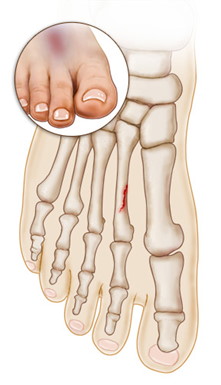

Stress fractures are the result of repeated application of stress to the bones—hence the name. Our feet, which hold all of our body weight, are under continuous stress every day, making them particularly susceptible to this type of injury. Stress fractures are sometimes described as small cracks or hairline fractures in the bone.

Stress fractures can occur in any bone in our bodies, but our feet are the most common location. This type of fracture can happen to any of the foot bones but it mainly occurs in the second and third metatarsal bones, in the navicular bone and in the calcaneus (heel bone).